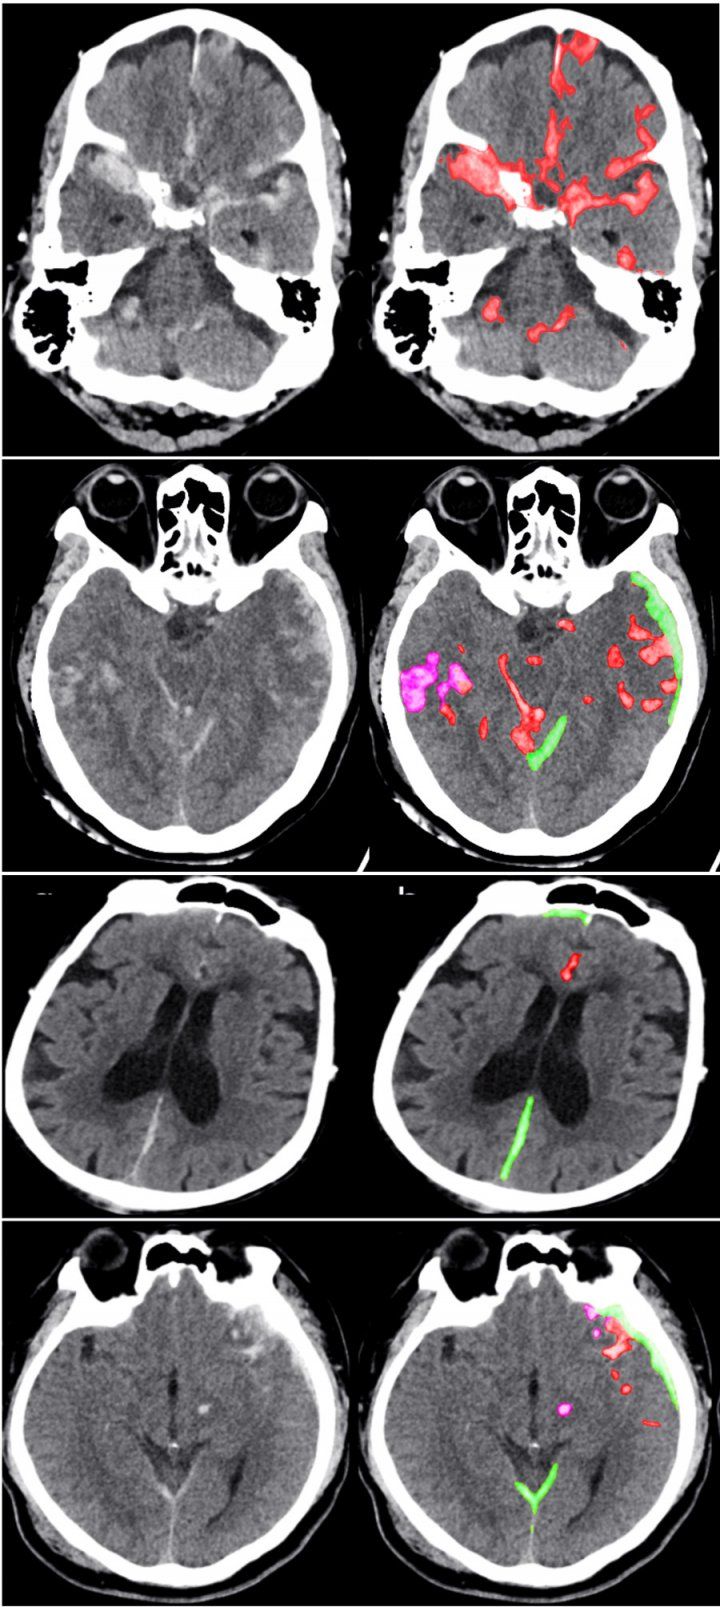

The algorithm the team developed took just one second to determine whether an entire head scan contained any signs of hemorrhage. It also traced the detailed outlines of the abnormalities it found—demonstrating their location within the brain's three-dimensional structure. Some spots may be on the order of 100 pixels in size, in a 3D stack of images containing over a million of them, and even expert radiologists sometimes miss them, with potentially grave consequences.

The algorithm found some small abnormalities that the experts missed. It also noted their location within the brain, and classified them according to subtype, information that physicians need to determine the best treatment. And the algorithm provided all of this information with an acceptable level of false positives—minimizing the amount of time that physicians would need to spend reviewing its results.

Jitendra Malik, PhD, the Arthur J. Chick Professor of Electrical Engineering and Computer Sciences at Berkeley, said the key was choosing which data to feed into the model. The new study made use of a type of deep learning known as a fully convolutional neural network, or FCN, which trains algorithms on a relatively small number of images, in this case 4,396 CT exams. But the training images used by the researchers were packed with information, because each small abnormality was manually delineated at the pixel level. The richness of this data—along with other steps that prevented the model from misinterpreting random variations or "noise" as meaningful—created an extremely accurate algorithm.